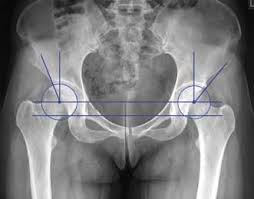

ДЕ ВИ БАЧИТЕ ЕЛЕМЕНТ КІСТКИ, ЗНАННЯ ЯКОГО НЕОБХІДНЕ В АКУШЕРСТВІ ДЛЯ ВИМІРЮВАННЯ РОЗМІРІВ ВЕЛИКОГО ТАЗУ? (ВЕРТЛЮГОВА ДИСТАНЦІЯ).

варіанти відповідей

ЯКОЮ ЦИФРОЮ ПОЗНАЧЕНИЙ ВЕЛИКИЙ ВЕРТЛЮГ? (В АКУШЕРСТВІ ВИМІРЮЮТЬ ВЕРТЛЮГОВУ ДИСТАНЦІЮ).

2

6

7

3

4

11

12